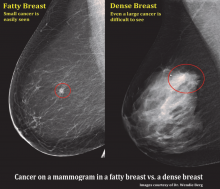

In addition to women with dense breasts, there are also other women for whom mammographic screening is not really enough, which is why research needs to continue in this field. Dr. Wendie Berg, a leading breast cancer specialist, talks with ITN about new research and advancements in breast imaging technology.

Dr. Berg, MD, PhD, FACR, FSBI, is Professor of Radiology at the University of Pittsburgh School of Medicine and Magee-Womens Hospital of UPMC, specializing in breast imaging. She is also the Chief Scientific Advisor to DenseBreast-info.org. A renowned expert, she writes and co-edits one of the leading textbooks on the topic, Diagnostic Imaging: Breast, currently in its third edition, and has co-authored over 120 peer-reviewed research publications.

It has long been said that a national reporting standard is needed in order to ensure all American women receive at least the same basic information regarding breast density, and a spotlight put on the importance of routine breast imaging. Dr. Wendie Berg, a leading breast cancer specialist, shares with ITN what is being done in the fight against breast cancer and the importance of this standardization in reporting for women.